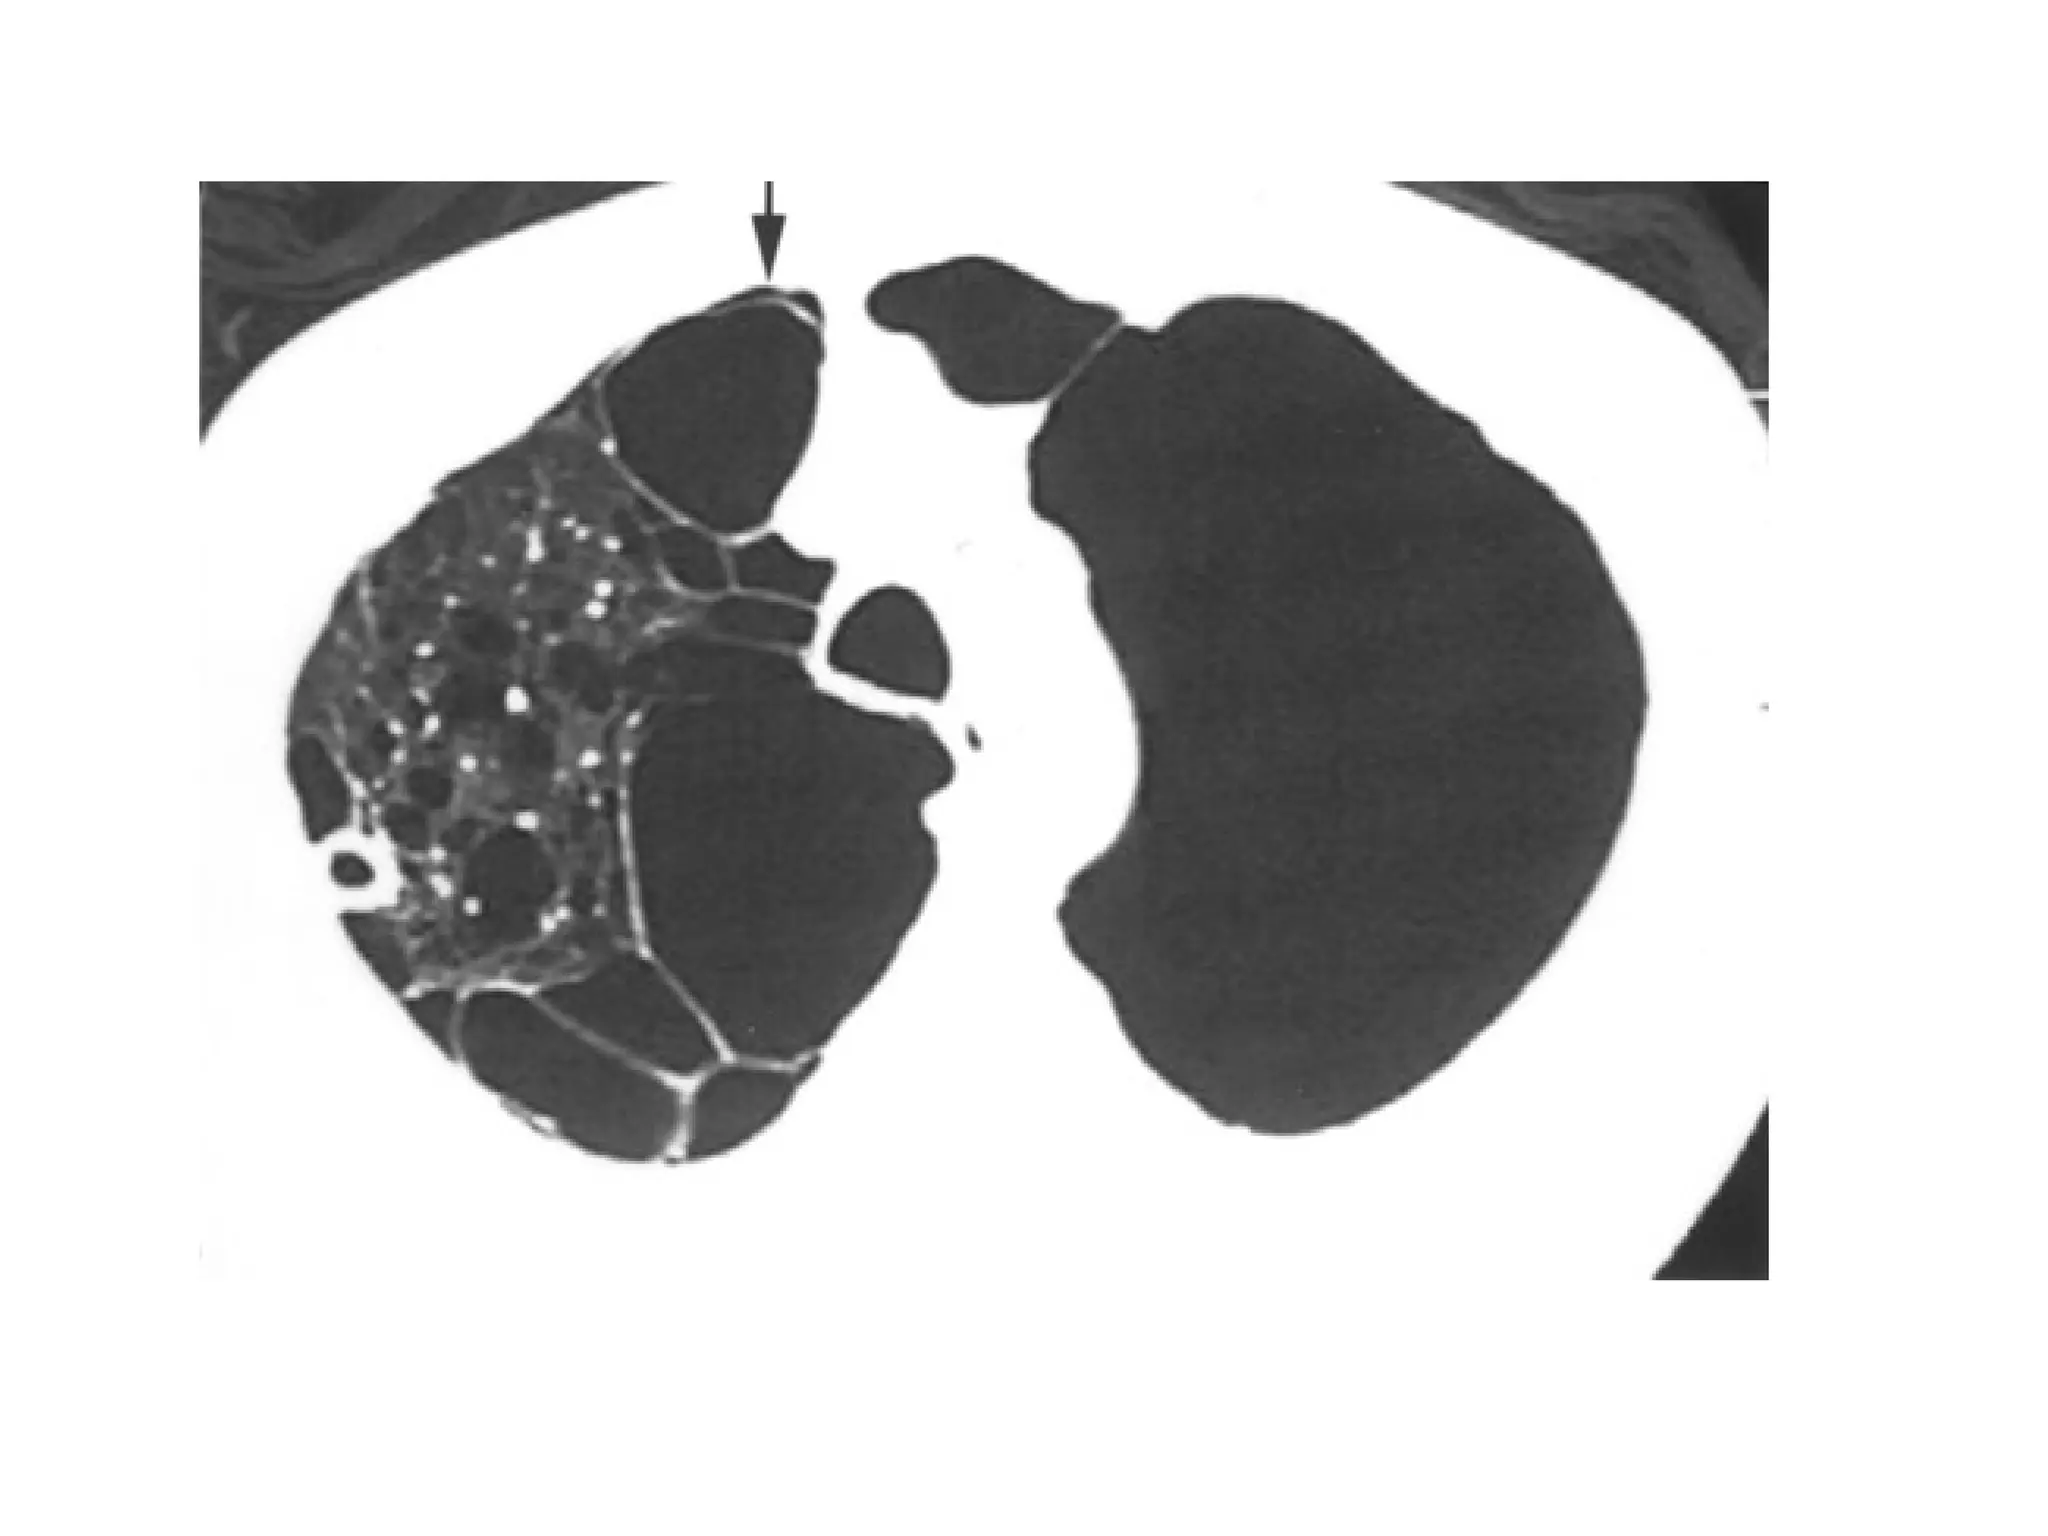

Bullous emphysematous lung

• Also called “Vanishing lung syndrome”

• Characterised by giant emphysematous bullae

commonly developing in upper lobe and occupy at

least one-third of a hemithorax.